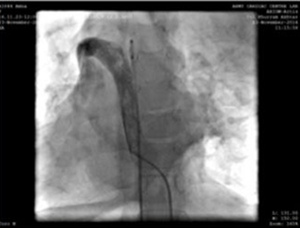

Правая бедренная вена и артерия канюлировали, использовали 5F радиальную оболочку. Во время процедуры мы обнаружили, что нижняя полая вена (IVC) стекает через азиготное продолжение в правую верхнюю полую вену, а затем отслеживает через расширенный коронарный синус в правом предсердии. Было принято решение о проведении процедуры из левой внутренней яремной вены (доступ к которой осуществляется с помощью радиальной оболочки 5F).

Прокол левой яремной вены и катетер для ангиографии 5F, показывающий вены плеча-верхняя полая вена-путь соединения правого предсердия.